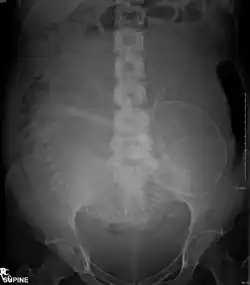

Exames de imagem na gravidez

Exames de imagem na gravidez podem ser indicados por causa de complicações da gravidez, doenças intercorrentes ou como parte da assistência pré-natal.